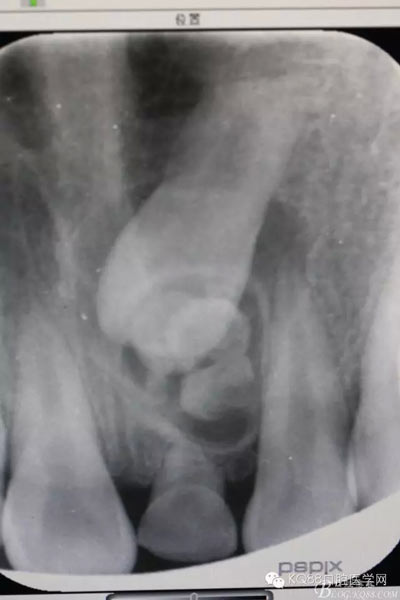

圖1.術(shù)前根尖片影像檢查:21根尖1/3彎曲,牙冠上方有一致密團塊影。左乳Ⅰ滯留